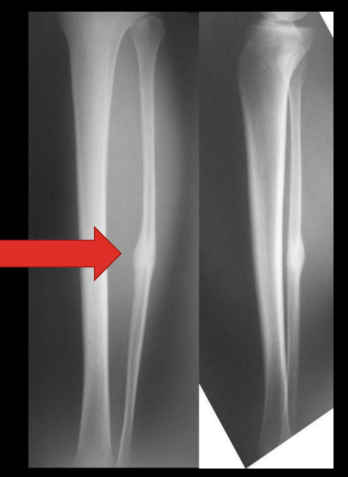

a callous following a fracture (increases//decreases) the area and polar moment of inertia during the healing process

increases

(later excess bone is re-absorbed as bone returns to normal strength)

nice lecture pic of bone healing and polar moment of inertia